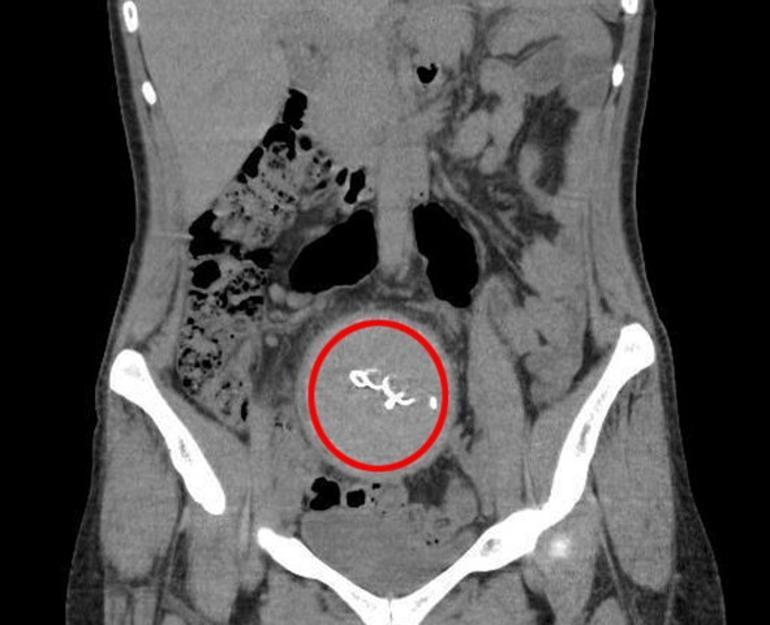

Burada yapılan kontrolde doktor acil tomografi çektirmesini istedi. Çekilen tomografide Y.S.’nin vücudunda doğum sonrası unutulan sargı bezi görüldü. Büyük şok yaşayan Y.S., 2 yıldır yaşadığı ağrılara ihmalin sebep olduğunu öğrendi. Y.S.'nin karnında unutulan yaklaşık 30 santimetre uzunluğundaki gazlı bez ameliyatla çıkarıldı. Y.S., hastane ve doktor hakkında hukuki süreci başlatması için avukatı Hasret Baş’a başvurdu.